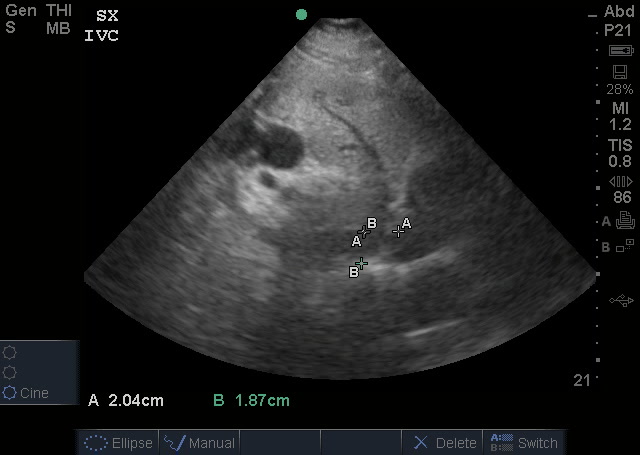

Gallbladder measurements:

The normal gallbladder measurements are an anterior gallbladder wall of 3mm, a width of 4cm and a length of no more than 9-10cm. The common bole duct (not measured) should be 6mm at the age of 60yrs (adding a mm for every decade above 60). The above image also shows a small amount of sludge but no obvious gallstone (it may have went into the bile duct and obstructed there). So, putting it together – this is obviously abnormal and evidence of acute cholecystitis.